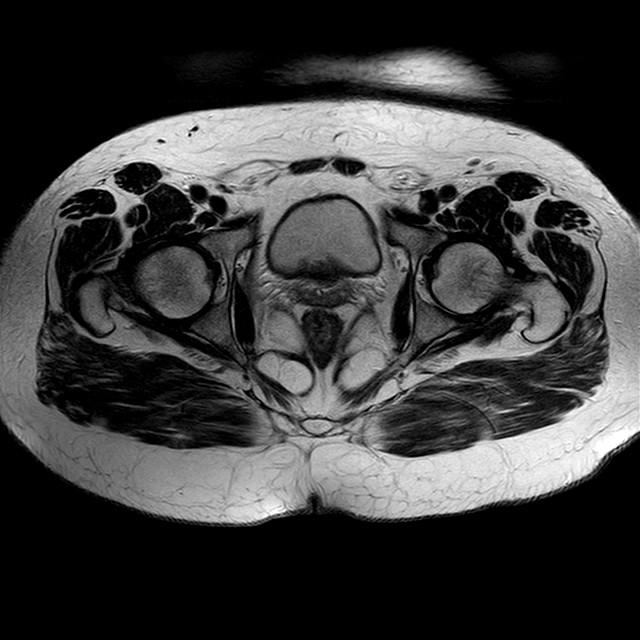

Esami: RMN BACINO

eT2w TSE

Evidenti e simmetriche alterazioni osteofitosiche in regione coxo femorale con riduzione delle rime articolari. Degenerazione completa del cercine glenoideo. Non attuali segni di versamento articolare. Non segni di edema osseo che escludono attuale algodistrofia od osteonecrosi. Lieve e simmetrica riduzione del trofismo della muscolatura glutea.